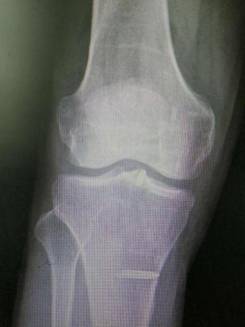

全膝表面置换术治疗重度骨关节病

优点:疗效可靠,膝关节病的最终解决方案。

胫骨高位截骨治疗膝关节骨关节炎

优点:创伤小,疗效确切,适合生活方式活跃的年轻患者。

关节镜下微创治疗胫骨平台髁间嵴骨折

优点:创伤小,康复快。